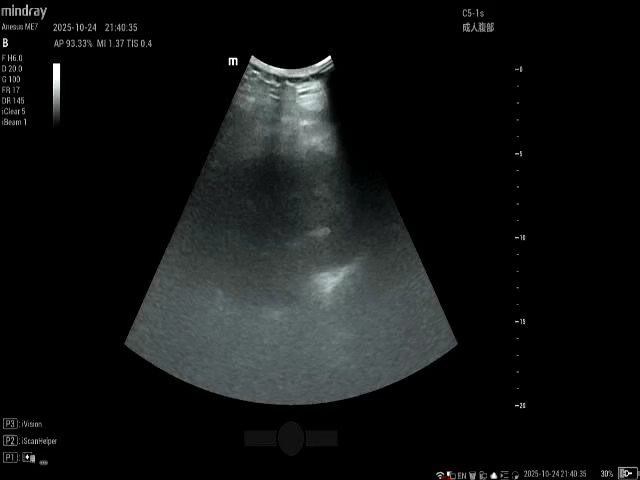

行泌尿西B超:

再次入院,哌拉西林舒巴坦抗感染,体温无明显下降,建议患者穿刺造瘘,从中午12点入院,间断谈话到晚上9点才穿刺。B超穿刺显示不清晰,全凭经验运气。